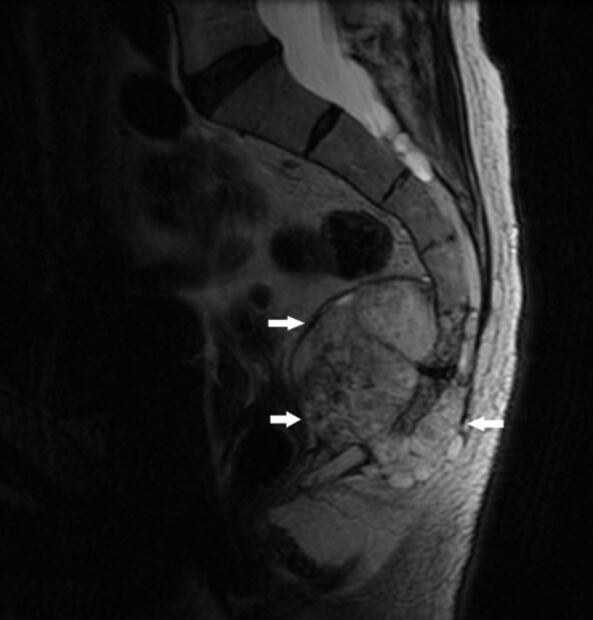

Imagen que muestra un tumor cerca del extremo de la columna vertebral. RM: Michael J. Joyce, MD, y Hakan Ilaslan, MD. Manual de Merck MSD

La influencer padeció sarcoma de Ewing, un tumor maligno que por lo general se desarrolla en los huesos y en los tejidos blandos que los rodean. Además, suelen aparecer en las extremidades, aunque puede afectar cualquier hueso.

De acuerdo con el Manual de Merck de Información Médica General, dicho sarcoma también se relaciona con tumores neuroectodérmicos primitivos periféricos (TNEP) y tiende a ser extensivo, los síntomas más comunes son dolor e hinchazón.